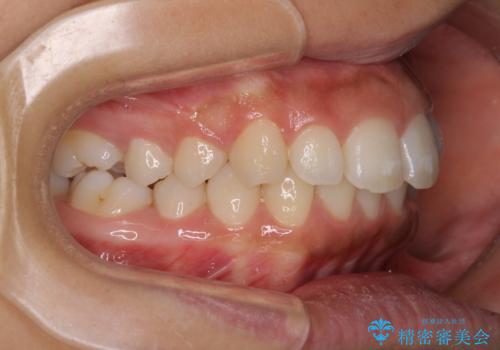

- 出っ歯で唇が閉じにくいとのことで来院された患者様です。

顎先に力を入れないと唇が閉じきれない口元であったので、上下左右の第一小臼歯4本を抜歯して、ワイヤー装置にて矯正治療を行うこととしました。

2年から2年半の治療期間を想定しており、予定通りの期間で無事に終了することができました。

唇や顎先に力を入れないなくてもスムーズに唇を閉じることができるようになりました。